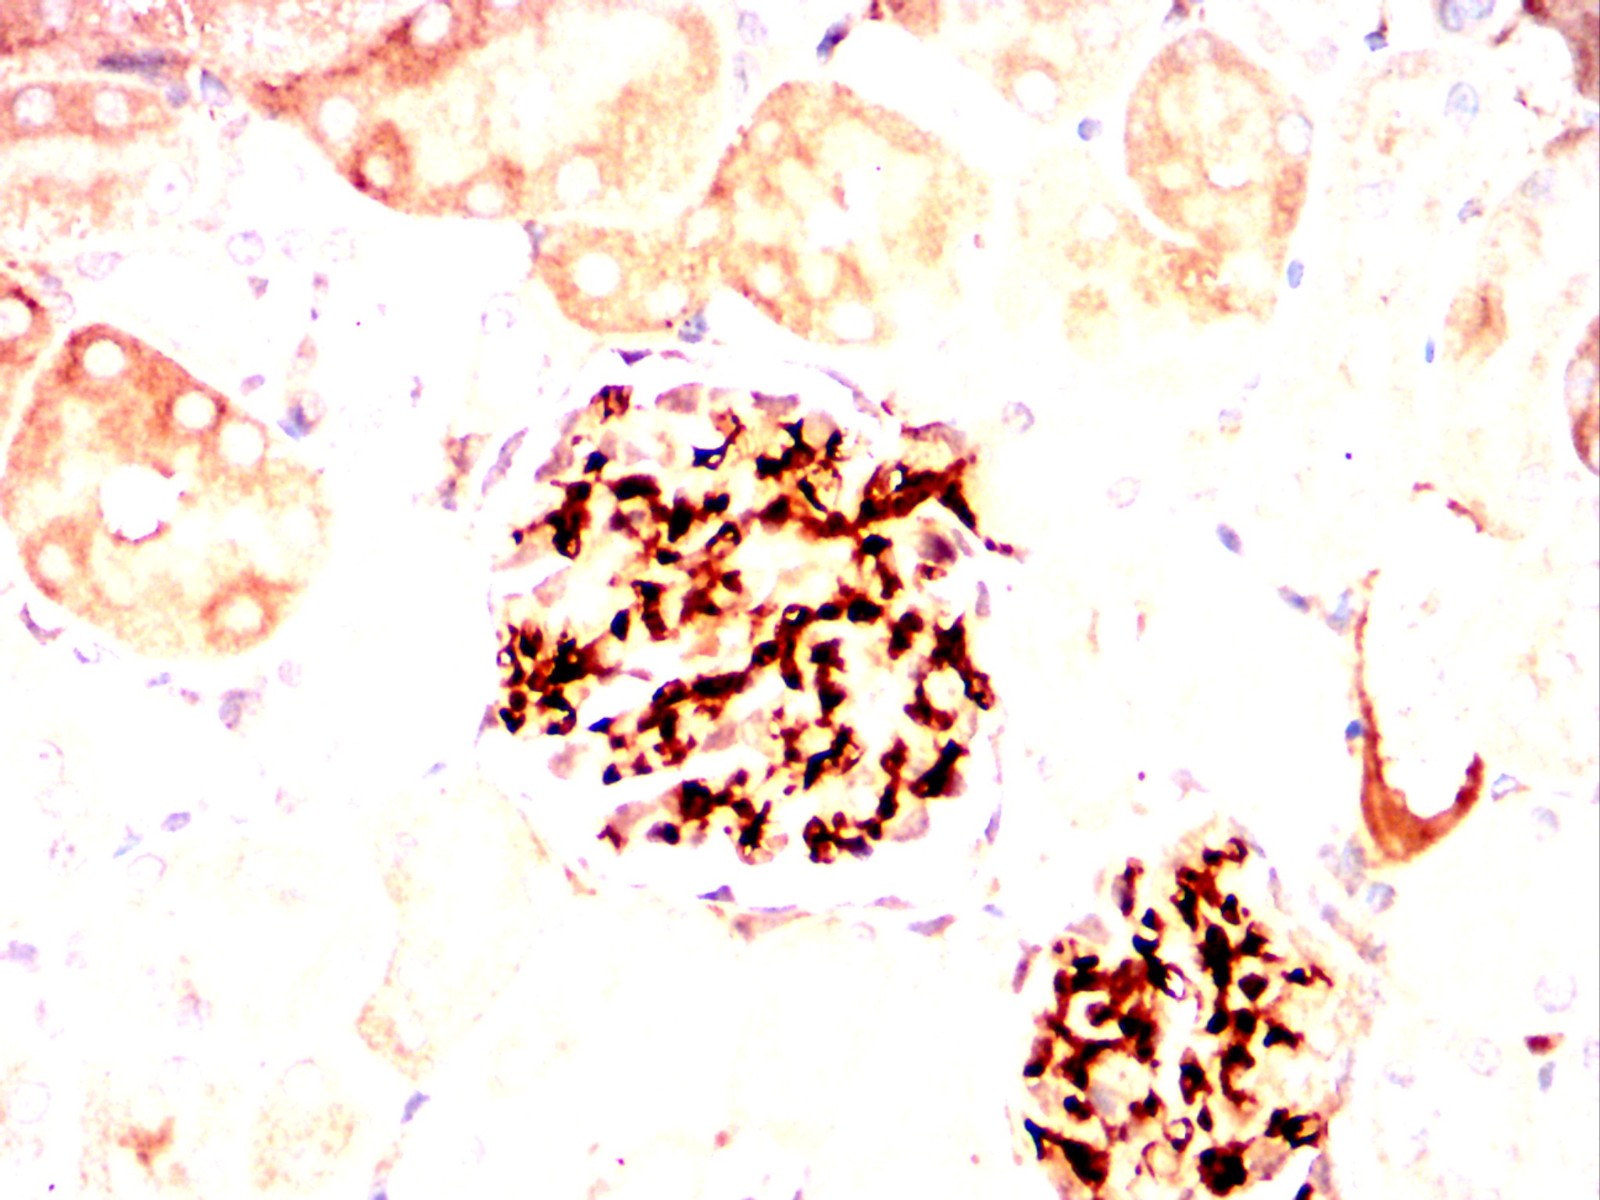

Immunohistochemical analysis of paraffin-embedded Rat kidney using AVP mouse mAb with DAB staining